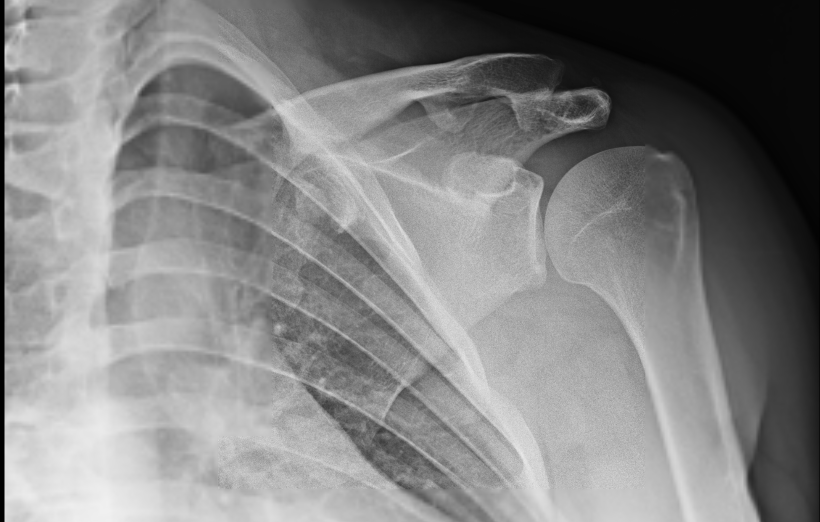

Patient is a 32 year-old male and has complaints with his left shoulder, neck and back pain after getting involved in a motor vehicle accident. Per patient, neck and back pain is tolerable but his shoulder is in extreme pain. We decided to get Xray for us to see the reason behind it. X Ray impression showed Acromioclavicular joint arthropathy.

MRI of the shoulder